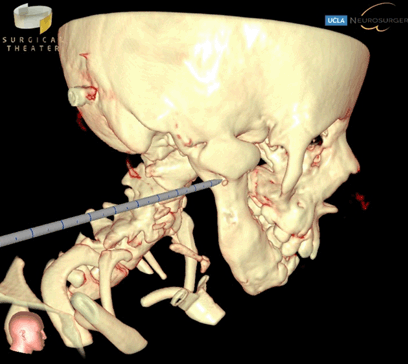

Prior to her last surgery, the patient had reankylosis of her bilateral TMJ resulting in severe limited jaw opening that required repeat mandibular osteotomies (Figure 1). For the previous mandibular osteotomy, Brainlab intraoperative CT-guided navigation system was used to aid in the preoperative planning of localizing and assessing the extent of the TMJ fusion. The surgery was completed in nine hours with no complications. For most recent mandibular osteotomy, SuRgical PlannerTM was used in conjunction with Brainlab intraoperative CT-guided navigation system (Figure 2). This additional surgical guidance tool allowed us to rehearse the operation for TMJ resection and also assess the extent of our dissection, thereby accelerating operative efficiency (Figure 3). Additionally, based on principle of CT scanning Hounsfield unit, the SRP simulator can display or hide slices of tissue in real time, thereby allowing us to visualize surrounding skull base, vessel, and soft tissue anatomy as well as the location of our surgical probe to minimize skull base complications [12]. Overall, the operative time was four hours, a notable decrease from nine hours previously. There were similar scars noted from prior surgeries and no complications. The exact same sequence of surgery and placement of Matthews device was performed for these two operations to justify the comparison.

Figure 2: Lateral profile view showing 3D precision VR instrument probe and intraoperative identification of narrowest location of the fused temporamandibular joint.